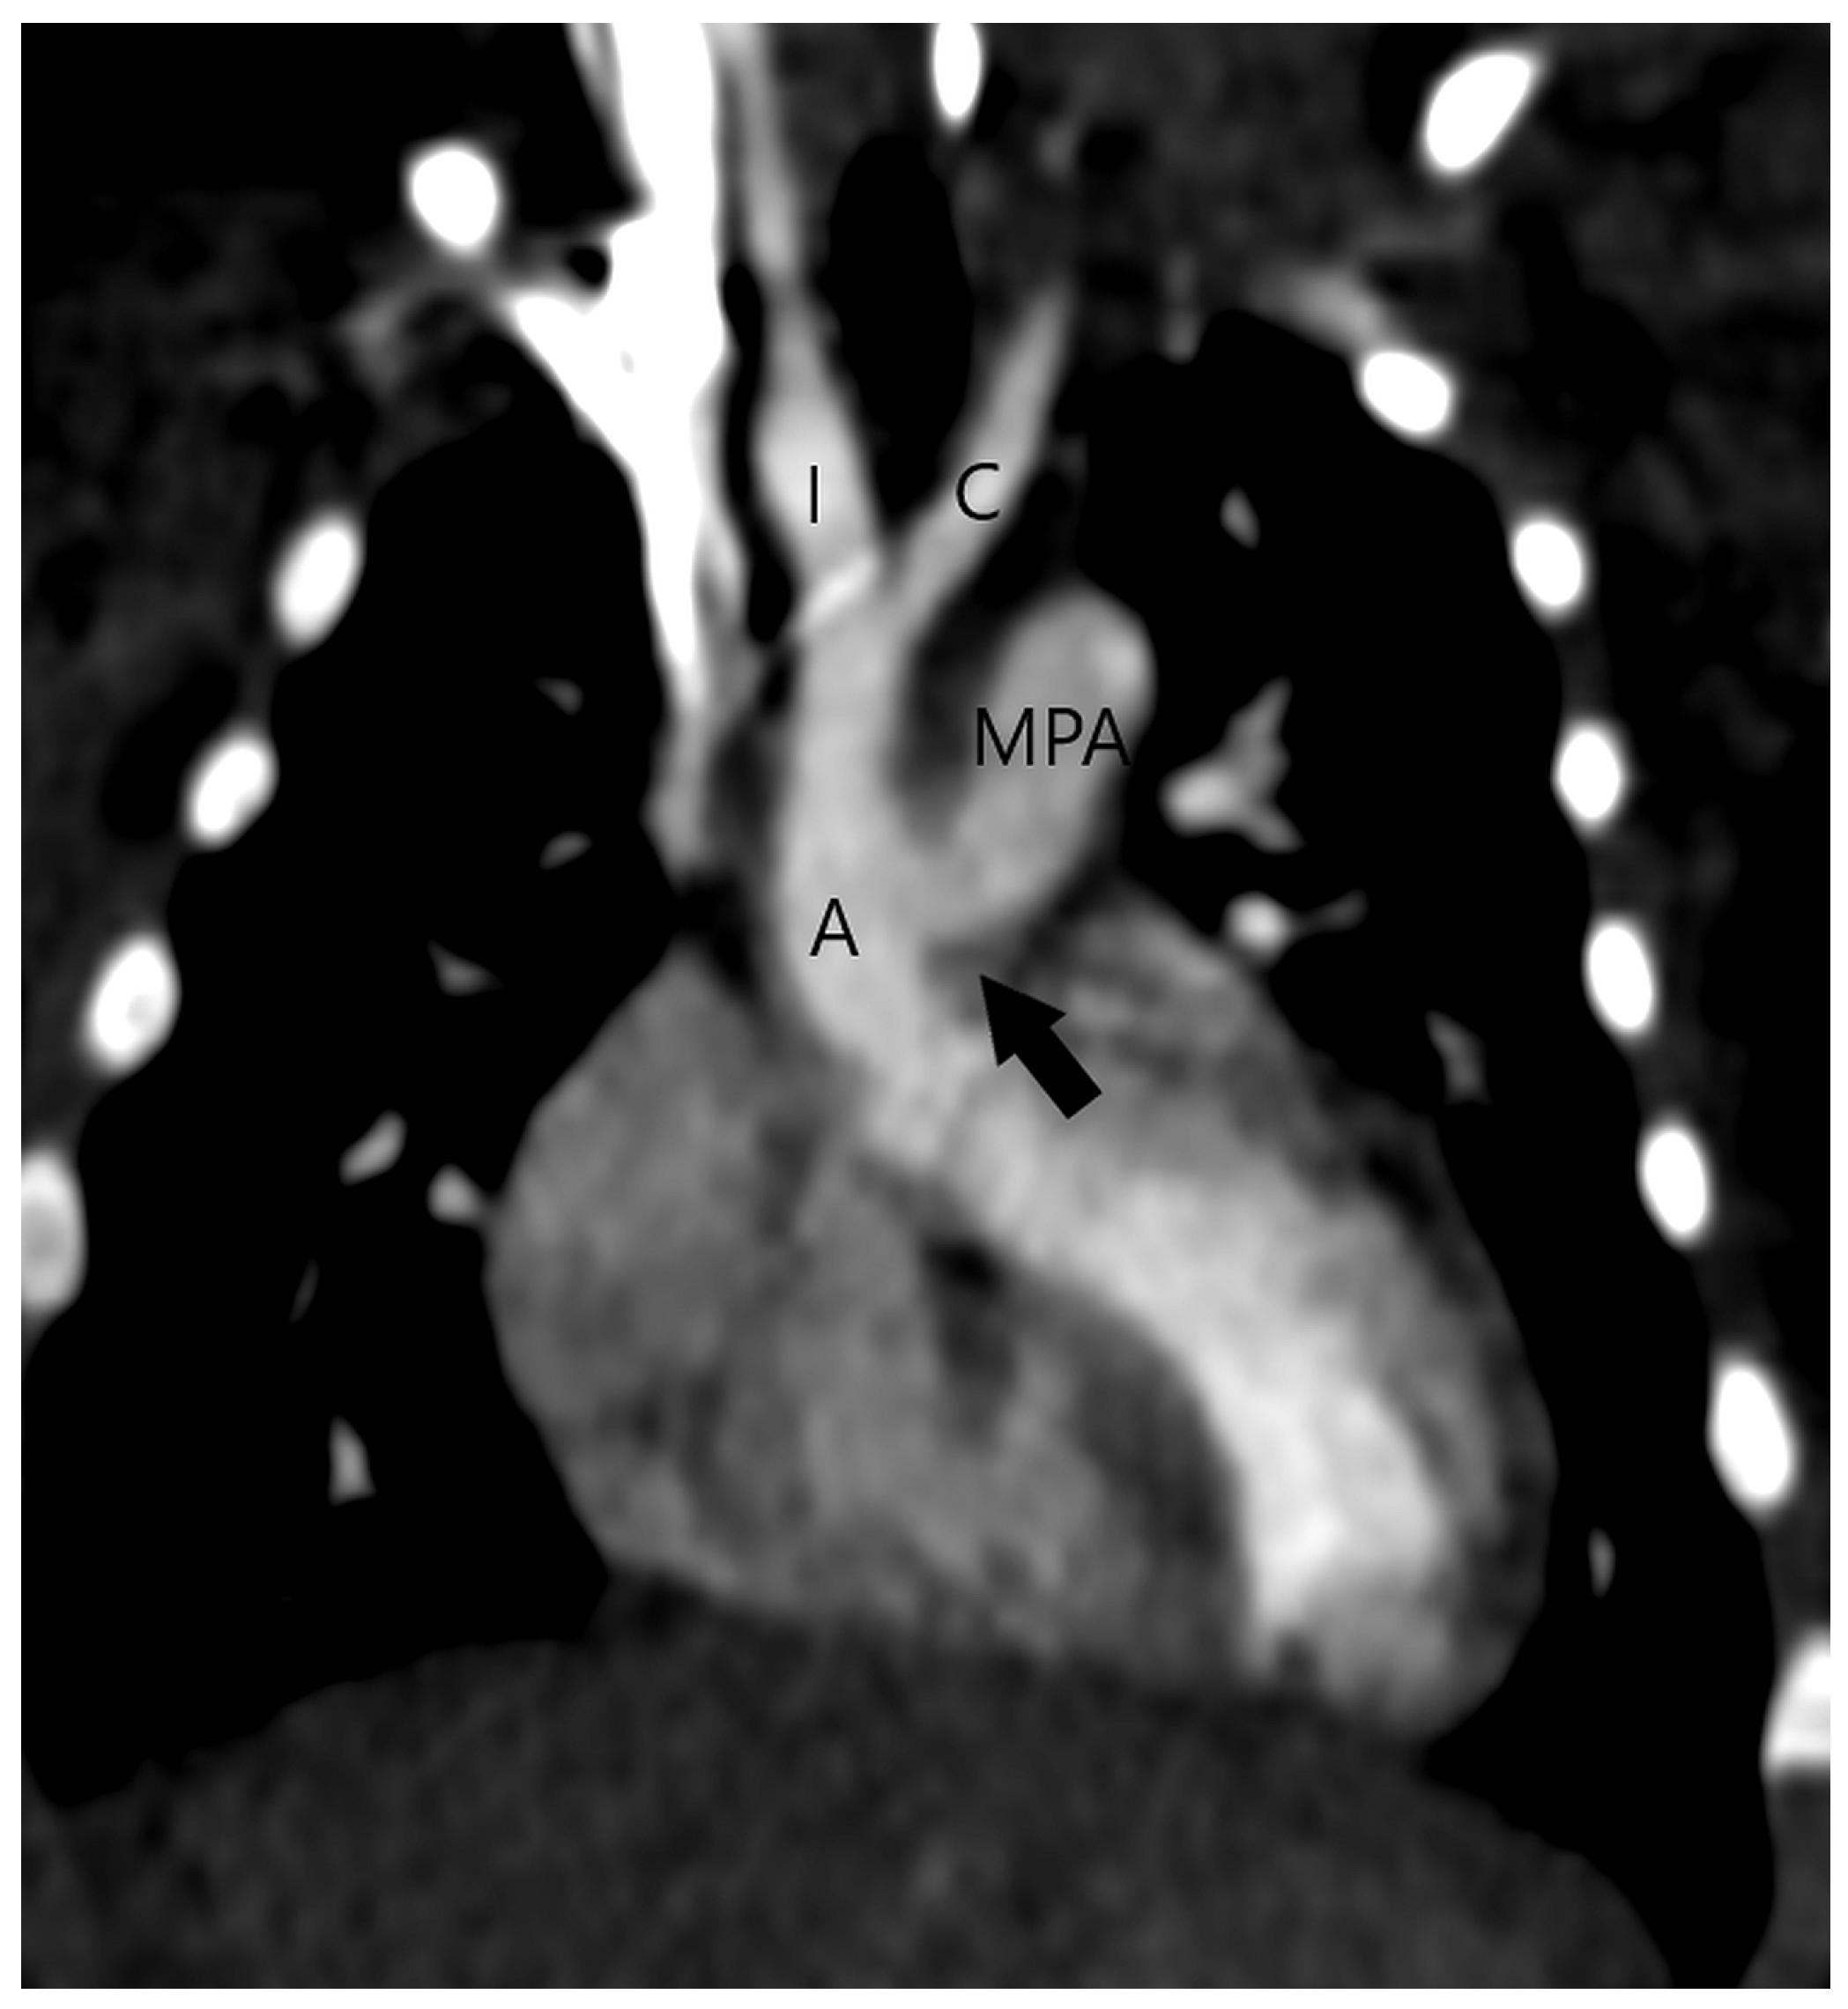

Figure 2.

Type 1 or proximal type of aortopulmonary septal defect (arrow) is located just above the semilunar valve between the ascending aorta (A) and the right wall of the main pulmonary artery (MPA) (A). The right-sided aortic arch can also be detected. After surgery, the ascending aorta (A) and the main pulmonary artery (MPA) are separated (B).